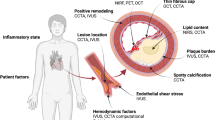

The healthy endothelium forms a barrier between blood flow and the arterial wall, senses the different types of biomechanical forces, and regulates numerous mechanisms of vascular homeostasis such as vascular tone, transportation of molecules, coagulation state and fibrinolysis. In atheroprone regions, and in the presence of coronary disease risk factors, vascular smooth muscle cells (VSMCs) migrate into the intima, proliferate, and elaborate molecules into the extracellular matrix (ECM) environment. Interaction of low-density lipoprotein (LDL) particles with ECM components, especially proteoglycans, facilitates the sub-endothelial retention of LDL long enough for their oxidation by reactive oxygen species (ROS). This reaction further augments endothelial dysfunction and triggers inflammatory pathways that result in monocyte recruitment, internalization, and differentiation into macrophages [9].

A continuous feedback between activated macrophages, dysfunctional endothelial cells, VSMCs, and LDL particles potentiates and aggravates the atherosclerotic process that gradually leads to plaque formation. Accumulated extracellular lipoproteins in the proteoglycan-collagen enriched ECM form the initial progressive atherosclerotic lesion, pathologic intimal thickening (PIT). The infiltration of macrophages within the lipid pool (accumulated lipoproteins) and their subsequent apoptosis result in the development of the lipid-rich necrotic core that, combined with a collagen fibrous cap, constitute the advanced lesion, a fibroatheroma [10].

Neovascularization, or formation of new vessels in the arterial wall, contributes to the progression of atherosclerosis, and is mainly triggered by the hypoxia attributed to intimal thickening and increased plaque size. The formation of new vessels provides the atherosclerotic lesion with oxygen and nutrient supplies and thus promotes plaque growth by reducing the limitation of diffusion distance; however, neovessels also supply inflammatory cells and pro-atherosclerotic molecular mediators to the plaque from the perivascular tissue. These newly formed vessels are also prone to rupture and hemorrhage due to compromised structural integrity related to a discontinuous endothelial layer and absence of smooth muscle cells [11, 12]. Intraplaque hemorrhage may also originate from subclinical plaque rupture or endothelial and fibrous cap injury [13]. This intraplaque hemorrhage constitutes a major contributing factor exacerbating plaque progression and instability since the free lipids from the red blood cell membranes and the released hemoglobin and iron lead to local fibrosis and scarring [14, 15]. Repeated cycles of subclinical plaque rupture and subsequent intraplaque hemorrhage may lead to progressively accelerated luminal obstruction clinically manifesting as worsening angina.

Arterial remodeling is another major determinant of plaque morphology and possible progression. Remodeling is an adaptive mechanism which reflects the ability of the vascular wall to adjust its dimensions in response to plaque growth or flow alterations. Positive or expansive remodeling denotes an increase in arterial dimensions, while negative or constrictive remodeling signifies that the arterial size decreases [16]. Compensatory expansive remodeling, as first highlighted by Glagov and colleagues in 1987 [17], is a process whereby the outer arterial wall enlarges to accommodate the plaque present within the arterial wall so that the lumen dimensions remain unchanged and distal blood flow is preserved. Excessive expansive remodeling, in contrast, is associated with highly inflamed atheroma, where the activated leukocytes elaborate plaque-degrading collagenases and elastases which disrupt the plaque structural integrity and lead to a focal excessive enlargement of the lumen and the arterial wall. These areas of excessive expansive remodeling have been consistently associated with high-risk plaque features leading to acute plaque rupture and acute coronary syndromes [18].

The earliest type of atherosclerotic lesion encountered in the coronary arteries is the PIT which is formed of smooth muscle cells arranged in layers in an ECM composed of proteoglycans and collagen fibers that overlie a lipid pool rich in low density lipoproteins, with variable infiltration of macrophages, presence of cholesterol clefts, and microcalcifications [19]. Fibroatheromas are composed of a necrotic core covered by a thick fibrous cap of smooth muscle cells and matrix of proteoglycans and collagen fiber types I and III [20]. Thin-cap fibroatheromas (TCFAs) are typically regarded as the precursor lesions responsible for adverse coronary events [7•] and are characterized by a large lipid and necrotic core, a thin fibrous cap and intense inflammatory cell infiltration [10, 21, 22]. The adverse clinical natural history manifestations of local atherosclerotic plaque may be triggered by a variety of pathobiological processes, such as endothelial denudation, fibrous cap disruption, intraplaque hemorrhage, endothelial dysfunction, and expansive remodeling [23–25].

Blood circulation through the coronary arteries and cardiac motion produces mechanical forces inflicted axially, radially, and circumferentially on the vessel wall. For computational purposes, these forces are better described as stresses, i.e., a force normalized by the area that the force is applied. ESS and tensile stress (TS) are the two stresses that critically modulate the atherogenic process and contribute to the regional and local heterogeneity of atherosclerosis [32–34]. Advances in computational techniques (computational fluid dynamics, finite element analysis) and intracoronary imaging modalities (intravascular ultrasound [IVUS], optical coherence tomography [OCT], coronary computed tomography angiography [CCTA]) allow for the in vivo estimation of hemodynamic forces [34, 35].

TS depends on hydrostatic (blood pressure), structural (lumen diameter, arterial wall thickness), and morphological (arterial wall composition) parameters. TS increases with higher arterial blood pressure, higher vessel lumen radius, and thinner arterial walls [36]. The composition and geometry of the arterial wall may alter TS values. According to experimental data, an increase in necrotic core size, a reduction in fibrous cap thickness, or the presence of microcalcification can increase TS [34, 37–40]. In addition, plaque regions with maximum lumen curvature such as the plaque shoulder are subjected to higher TS [37]. On the cellular level, TS affects VSCMs function including activation, migration, and apoptosis and, thus, contributes to atherosclerosis progression [41–44]. The distribution of TS along the length of a plaque and the site of maximum TS is of great interest as it correlates with the plaque rupture region [45].

ESS is the tangential force produced by the friction of the flowing blood to the endothelial surface and depends on blood viscosity and velocity. Low ESS (<1.5 Pa) provokes molecular, cellular, and vascular adaptations in areas prone to plaque development, leading to the initiation and progression of atherosclerosis [46]. The focal formation of lesions in specific predilection sites follows the different flow patterns created as blood circulates through the coronary tree. Arterial sites with curvatures, bifurcations, and upstream or downstream from obstructions exhibit disturbed local flow and low ESS in contrast to the laminar, undisturbed flow and physiologic (1.5–3 Pa) or high (>3.0 Pa) ESS in arterial segments that consistently exhibit a vasculoprotective phenotype. Endothelial mechanosensors sensitive to blood flow patterns and ESS stimuli can alter endothelial cell conformation and intracellular gene expression [47, 48]. Biomechanical stimuli act through intracellular mechanisms to activate a cascade of biochemical signals that modify gene transcription and expression through the anti-inflammatory transcription factor (TF) Kruppel-like factor 2 (KLF2) and the pro-inflammatory nuclear factor-κB (NF-κB) [49].